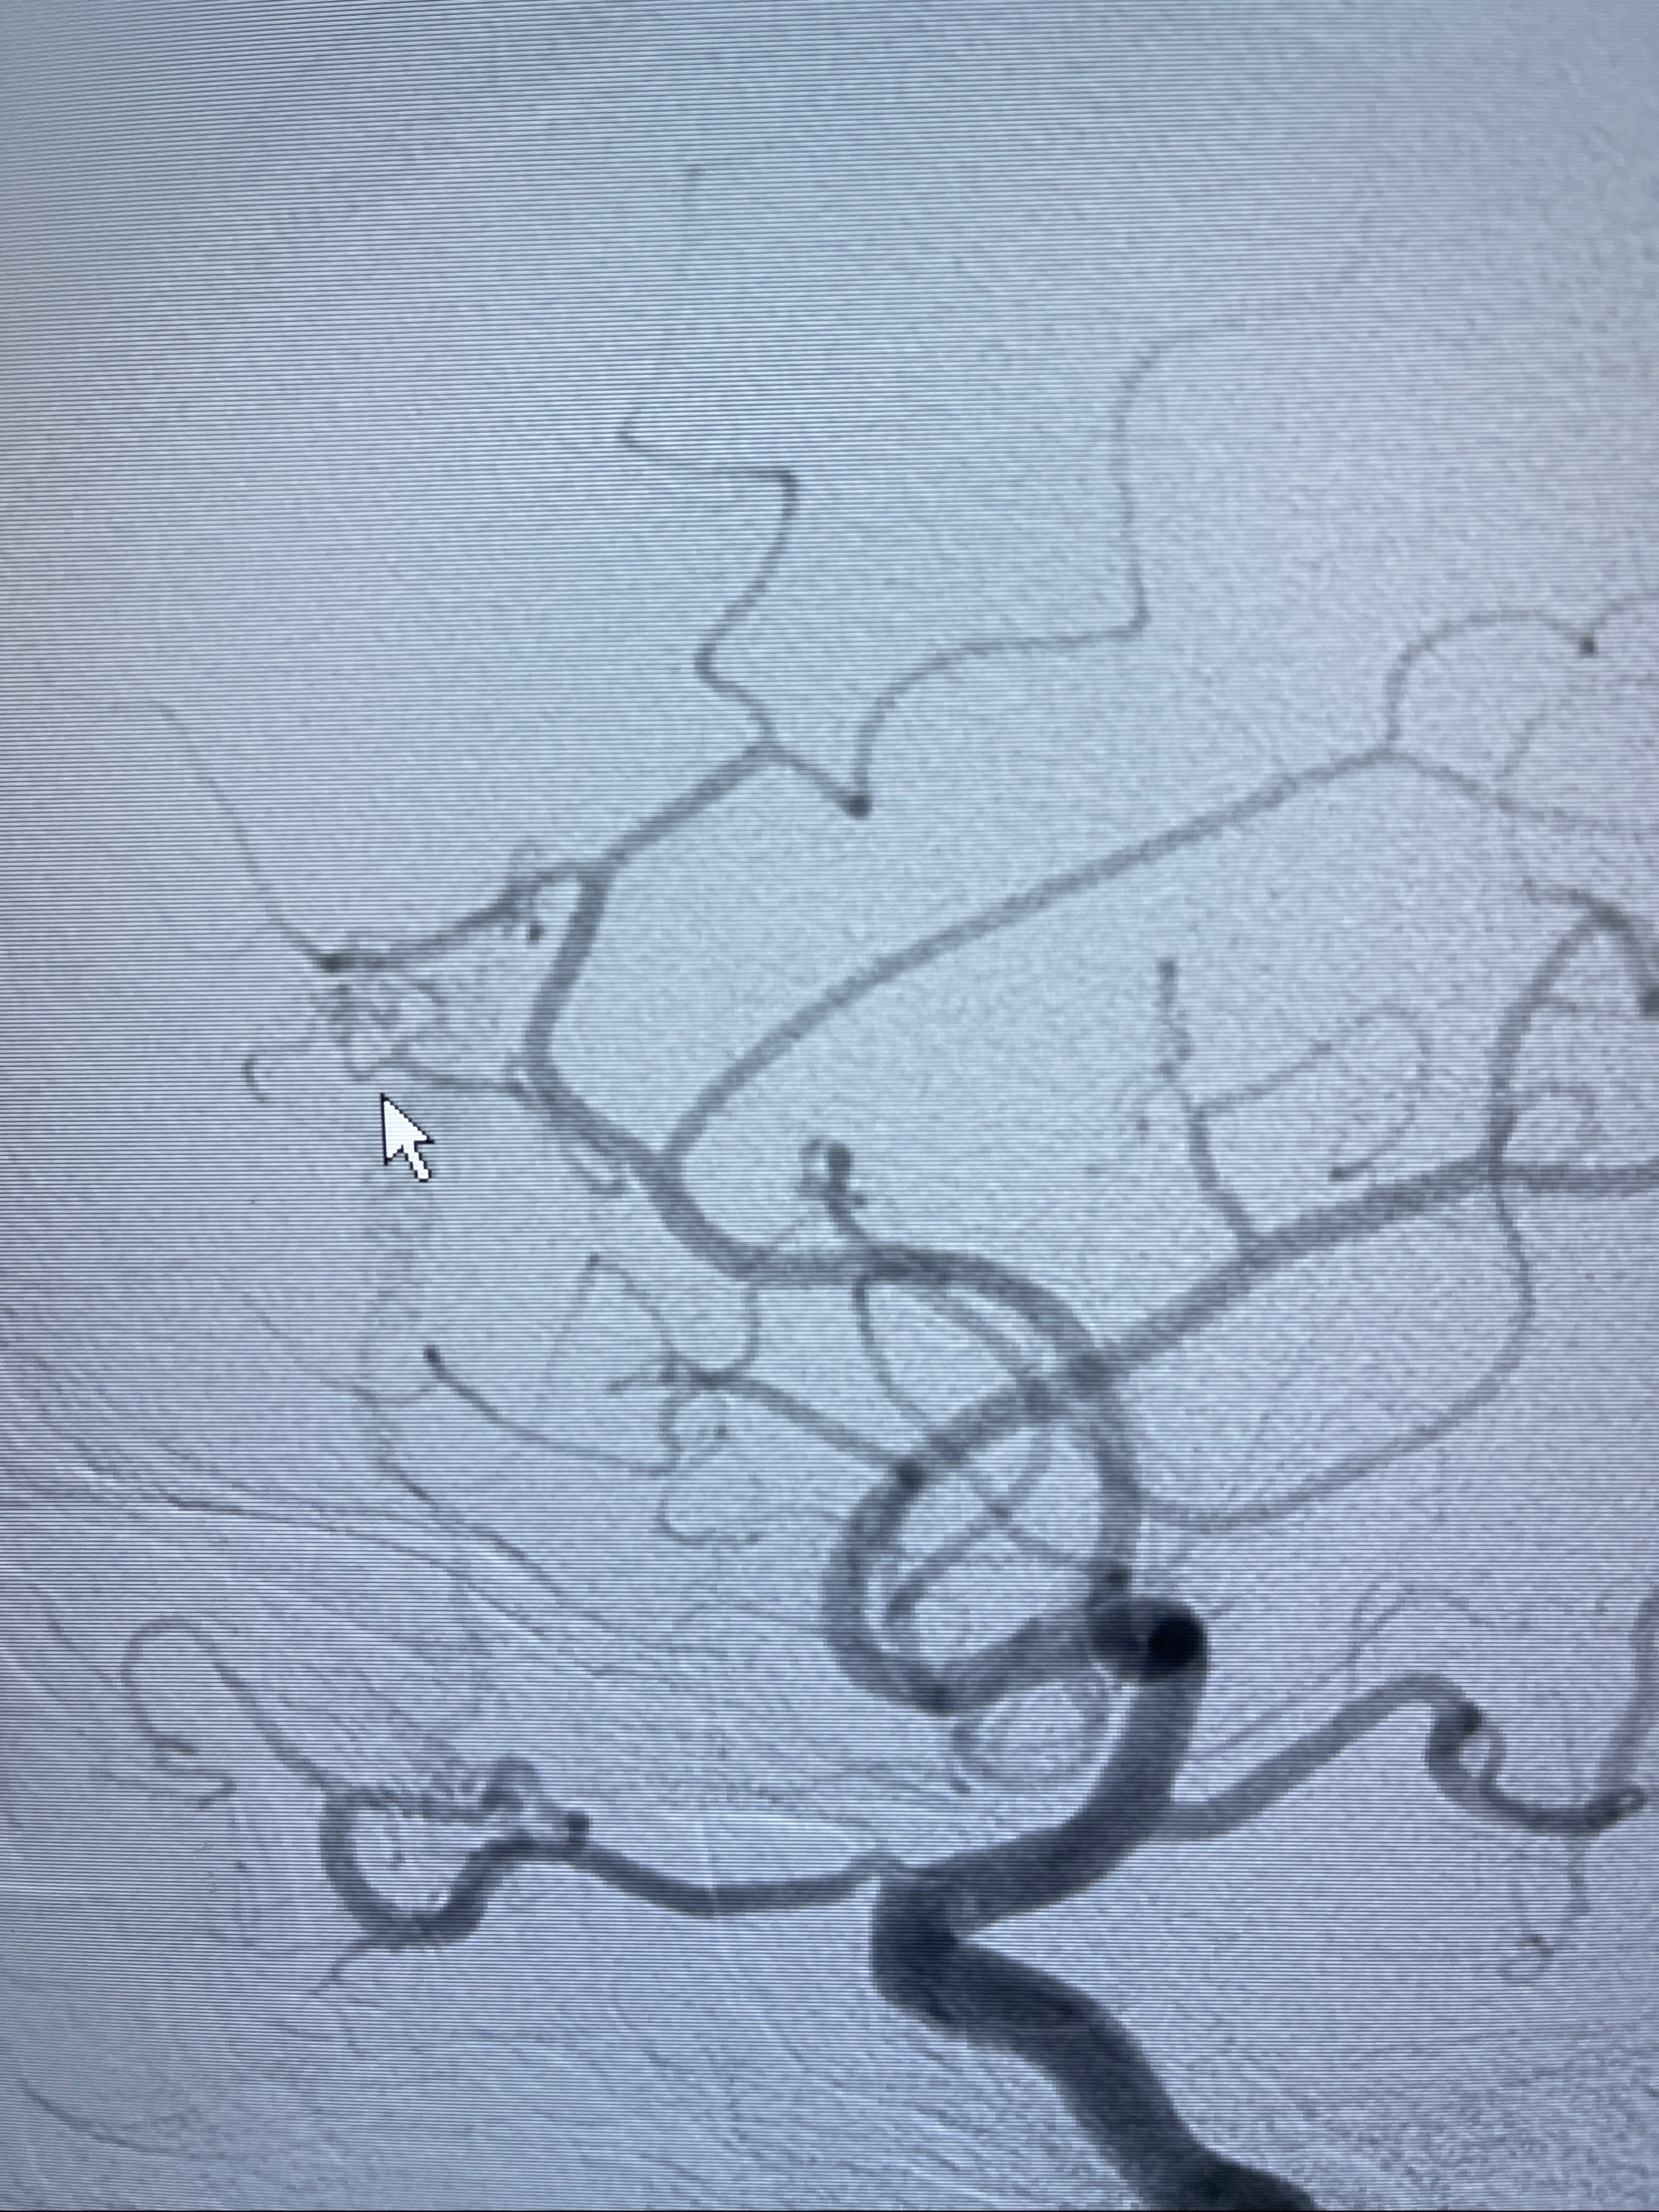

2023-09-13全脑血管造影:前颅底硬脑膜动静脉瘘,供血动脉为双侧胼周动脉、眼动脉脑膜支,静脉向上矢状窦方向引流